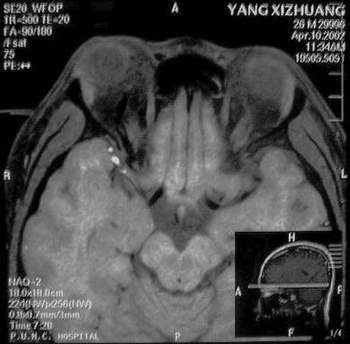

MRI及增强结果如下:

患者压颈及其它Valsava试验结果阴性。从MRI分析,在T1、T2、T+C检查该支血管均为明显流空现象,说明该血管血流速度很快,而从走行和分布看,眼上静脉可能性很大。也许也不能除外异常的眼动脉或异常血管。眶内主要可能的血管病变包括颈内动脉海绵窦瘘(高流窦)、AVM、眼眶静脉曲张、海绵状血管瘤、静脉性血管瘤、毛细血管瘤和眶内动脉瘤。。 1、颈内动脉海绵窦瘘:该患者临床有一部分支持该诊断。但从影像分析,海绵窦未见明显扩张;眼外肌未见明显充血扩张的长T1、长T2信号;颈内动脉海绵窦瘘常可见继发到血栓,可见到短T1、长T2的血栓信号。 2、眼眶静脉曲张:该疾患一般常见于小儿。该患大多数会出现Valsava试验阳性,间歇性突眼。不符合该患。影像学检查,于曲张静脉内常可见血栓和静脉石。所以不符合该患。 3、AVM:患者目前的影像学资料尚不全面,但可符合该诊断。临床上改病常见于30岁左右年轻人,单侧发病,于本患较符合。问题在于临床没有明确的血管杂音,似乎难以解释。 4、该患影像学与海绵状血管瘤差别很大,所以可基本排除此诊断。 5、静脉性血管瘤和毛细血管瘤:MRI中等T1、长T2信号,较易与本病鉴别。 6、眶内动脉瘤:我觉得患者并不能排除本病,但同样,由于波动性阴性,似乎也难以解释。 纵上所述:本人觉得,患者AVM可能性较大,同时不能除外眶内动脉瘤。 关于进一步检查,我觉得DSA价格过于昂贵。是否可先进行彩色多普勒检查,首先可以明确是静脉系统还是动静脉瘘抑或是动脉瘤。第二步,可进行MRA检查,可以清楚地显示海绵窦地相关关系,并可借此诊断或排除颈内动脉海绵窦瘘。如还需第三部检查,可进行MRV检查,对静脉系统进一步评价。三种检查总共的费用2000多圆,但给予我们的信息量已经很丰富了。 敬请各位医师提出自己的见解。 谢谢!